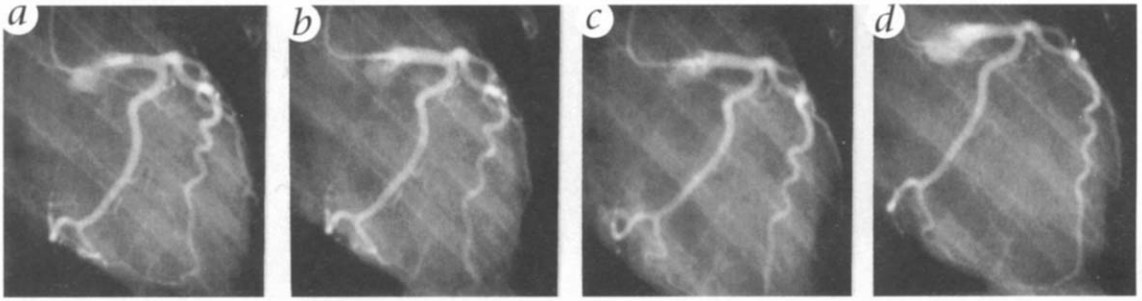

Angiographic examples at the point of peak responses to intracoronary (IC) vasoconstrictor challenges in the P group are shown in Fig. 1. Coronary arteries had normal dilator function, as shown at the lower dose of serotonin (Fig. 1, a and b) or with ACh. Even with the potent S+U challenge repeated six or more times, there was no vasospasm in the P group protected arteries (Fig. 1, c and d). However, there was vasoconstriction and decreased contractile function, as shown by decreasing blood pressure 3-10 minutes after injection and ST segment changes in the electrocardiogram (EKG), indicating myocardial ischemia. Vasoconstrictions to the S+U protocol in the P group never showed the vasospasm hallmark pattern of focal constriction with downstream dilation.

Figure 1. Coronary angiograms of an E2 + progesterone treated monkey show the control (a), dilation with low dose (100 μm) serotonin (b), constriction with 1 μm U46619 (c) and further constriction with the third repeat of 100 μm serotonin + 1 μm U46619 (d). Although there was strong coronary vasoconstriction that severely diminished cardiac contractility (a fall in systolic/diastolic blood pressure to 45/22 mm Hg; more than 30 s required to clear the radiocontrast media; and ST segment changes in the EKC that suggested extensive left ventricular ischemia) there was no vasospasm.